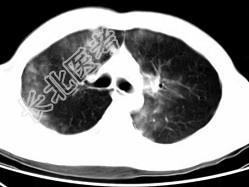

- 单项选择题男,28岁, 外伤后1小时行胸部CT如图,其最可能的诊断为 ( )

E、双肺挫伤